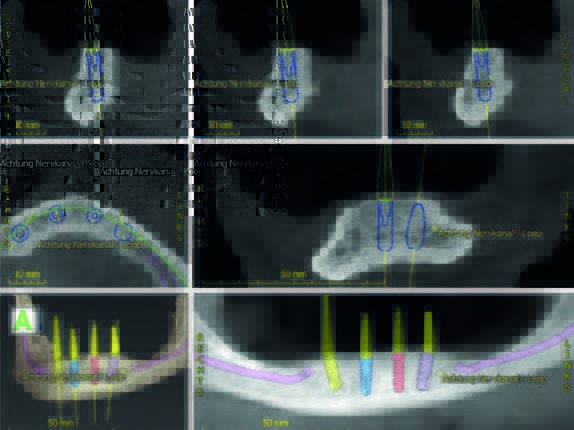

In Rahmen einer Fortbildungsveranstaltung wurde einem zahnlosen 81-jährigen Patienten (Abb. 8) mit geeigneter Indikation angeboten, das SynCone-Prinzip und die Anwendung des ATLANTIS Conus-Abutmentskonzepts kennenzulernen und damit den Fortbildungsteilnehmern Einblick in die direkte Anwendung zu ermöglichen (Abb. 9). Es erfolgte zunächst eine Duplierung der Unterkieferprothese als röntgenopake Bariumsulfatprothese. Nach der 3D-Planung (Abb. 10) und Herstellung einer gedruckten 3D-Schablone erfolgte der operative Eingriff in Lokalanästhesie unter intravenöser Single-Shot-Gabe des Antibiotikums Clindamycin 600 mg. Folgende Implantatsysteme kamen (von links nach rechts) zur Anwendung: Astra Tech EV (OsseoSpeed, Länge 13 mm, Ø 4,2 mm in regio 034), Straumann Bone Level (Länge 12 mm, Ø 4,1 mm in regio 32), Xive S (Länge 13 mm, Ø 4,5 mm in regio 42) und ANKYLOS C/X (C Länge 11 mm, Ø 5,5 mm regio 044). Die Bohrschablone wurde mit mehreren Osteosynthese-Schrauben auf ihrem Lager fixiert (Abb. 11). In typischer Art und Weise wurden die verschiedenen Implantate nach den Vorgaben ihrer Bohrprotokolle inseriert (Abb. 12-14).